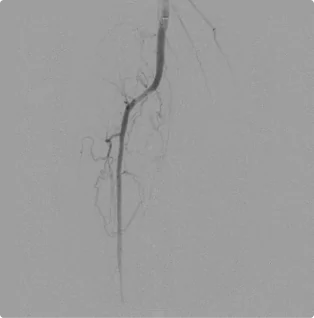

Female – Age 84

Referred by her Internal Medicine Physician for Both Suspected Venous and Arterial Disease

Diagnostic testing revealed that this patient had only one artery capable of delivering blood down the right lower leg. While two of the three arterial branches in the calf were completely blocked, one fragile artery (her peroneal) had the potential of properly delivering blood, glucose, and oxygen to the calf and foot. Still, it was almost entirely blocked as well. Through diligent atherectomy, angioplasty, stenting, and careful monitoring, Dr. Goldstein has kept her single lower leg artery open and kept her right foot alive. After treating her arterial disease, Dr. Goldstein and Dr. Hewett have treated her venous reflux disease successfully. They have continued to maintain and treat her arteries accordingly, allowing this active woman to keep traveling and enjoy a high quality of life.

Before

Before treatment, incomplete flow through the peroneal artery forced blood to seep into tiny arteries inside the calf to deliver blood to the starving tissue.

After

After treatment, the artery has clear, efficient flow down the calf into the healthy foot.